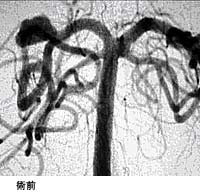

(3)頸動脈狭窄症に対するステント留置術

(現在、ステントは保険適応となっておりません。)